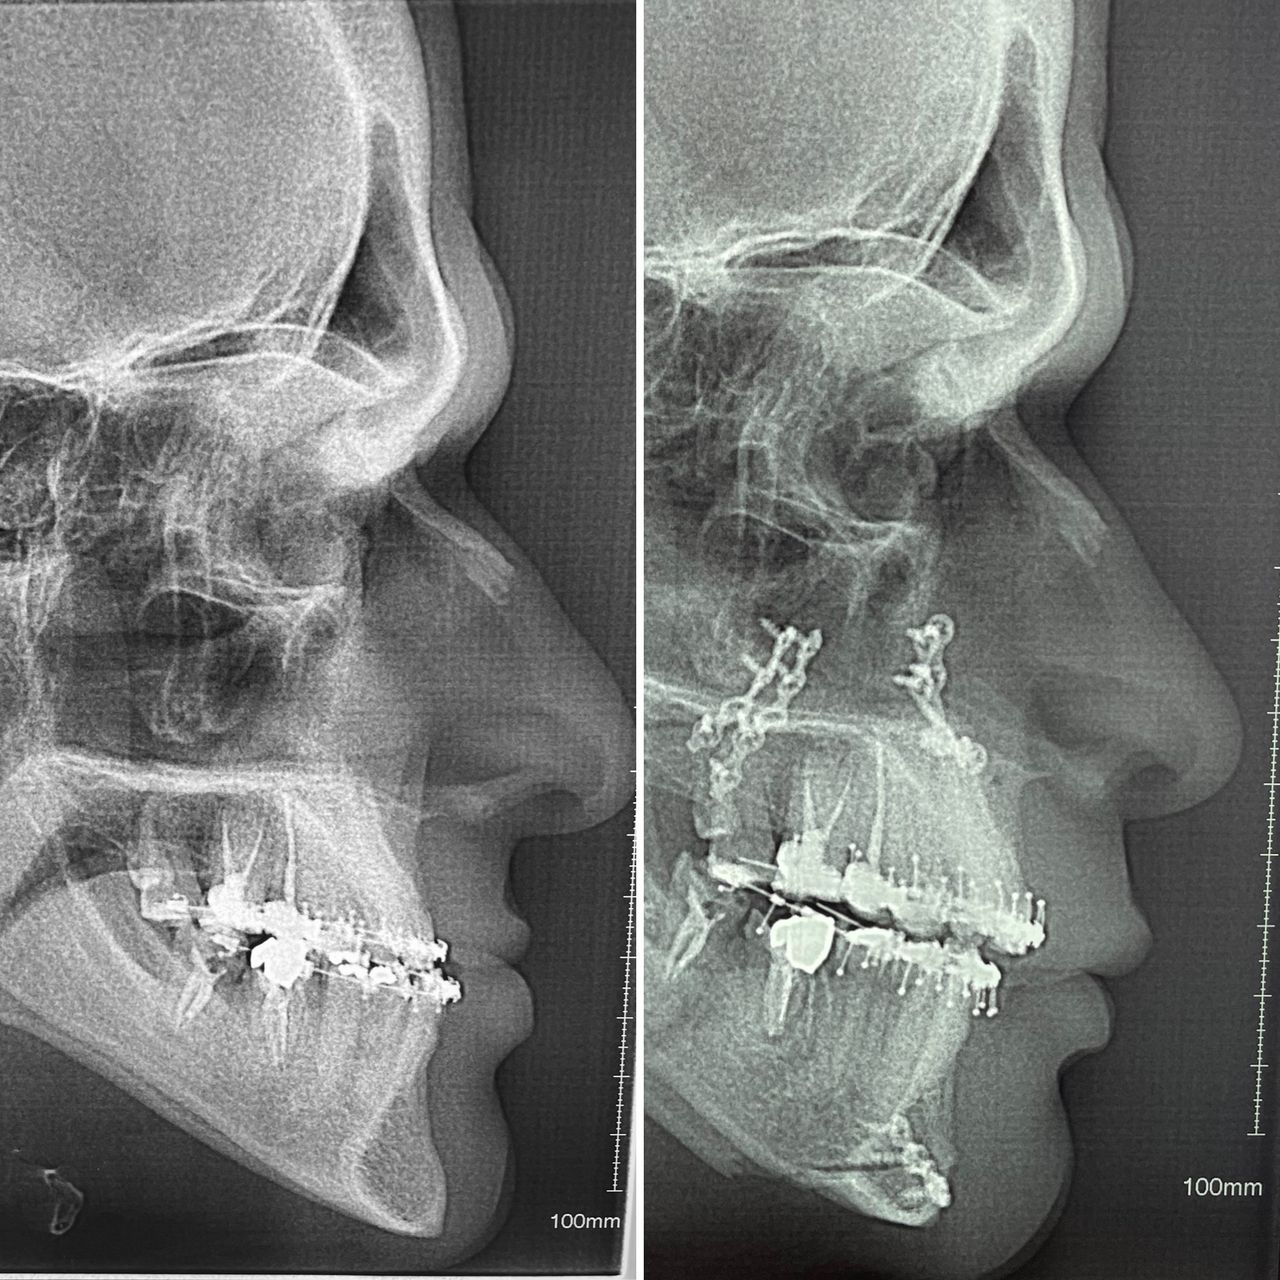

In the field of maxillofacial surgery, I have experience in the surgical management of facial trauma, dentofacial anomalies, temporomandibular joint dysfunction, mandibular reconstruction, facial cosmetic surgery, blepharoplasty, otoplasty, mentoplasty, facelifts, lip lifts and lip repositioning, removal of facial biopolymers, and orofacial harmonization.

- Cirugía ortognática